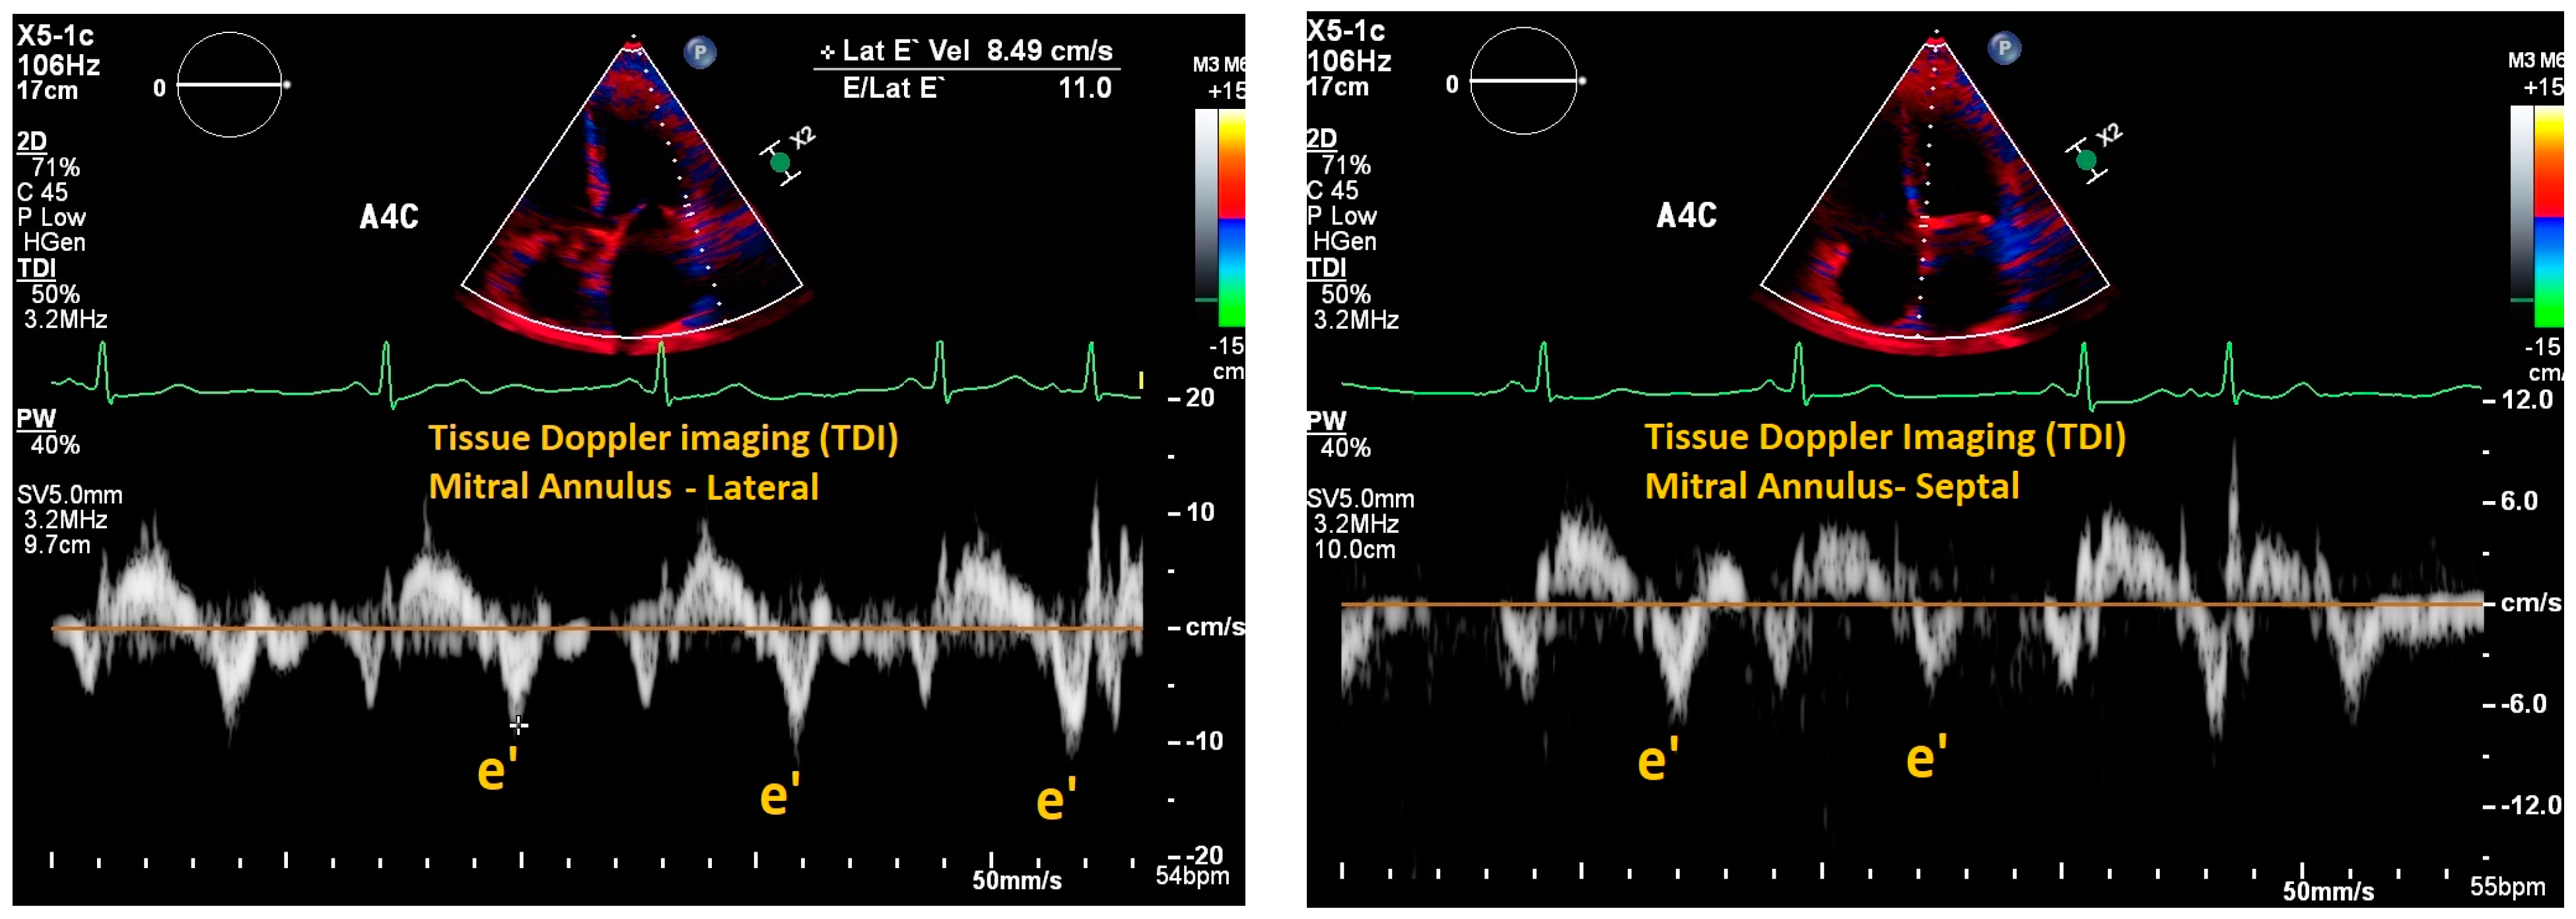

| Mitral E/e’ ratio estimated from the E wave velocity of the mitral inflow Doppler envelope and the tissue Doppler e’ wave velocity at the mitral annulus (septal and/or lateral) | E/e’ ≤ 14 |

|

| |

| Fletcher et al., 2020 [9] | Systematic review | Tricuspid inflow velocities | Patients with valvular disease, altered RV systolic function, recent cardiac surgery, acute heart failure, heart transplant, pulmonary hypertension, atrial fibrillation | Strength of correlation between E/e’ and RAP | 17 articles | Consistent positive correlation between E/e’ and RAP in patients with reduced RV systolic function; equivocal support correlating E/e’ and RAP in heart failure patients. |